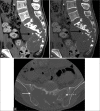

(a and b) Plain CT pelvis. Destructive sacral lytic lesion with soft-tissue mass containing intratumoral calcifications. (c) Plain CT pelvis. The mass eroded the right sacral foramen, extended across the right sacroiliac joint, and invaded the right iliac bone (white arrow). It also extended to the left sacroiliac joint (white dotted arrow).